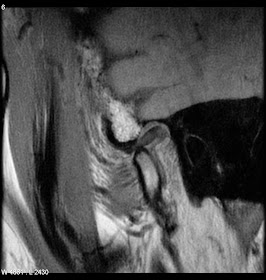

A partially circumscribed retroareolar mass in a male with suspicious microcalcifications; this is known breast cancer.